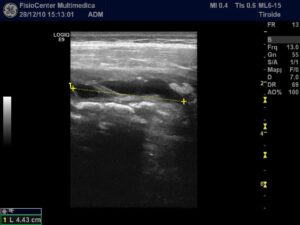

28.12.2010

In corrispondenza del terzo prossimale del muscolo retto femorale di destra si osserva area anecogena a margini netti che misura 44,3 mm. in scansione longitudinale.

Quadro compatibile con versamento, verosimilmente ematico, secondario a trauma contusivo diretto.

11.01.2011

In corrispondenza del terzo prossimale del muscolo retto femorale di destra si osserva completa risoluzione del versamento precedentemente riscontrato.

Si consiglia ripresa sportiva graduale (idrokinesiterapia, esercizi isometrici e poi training concentrico/eccentrico).